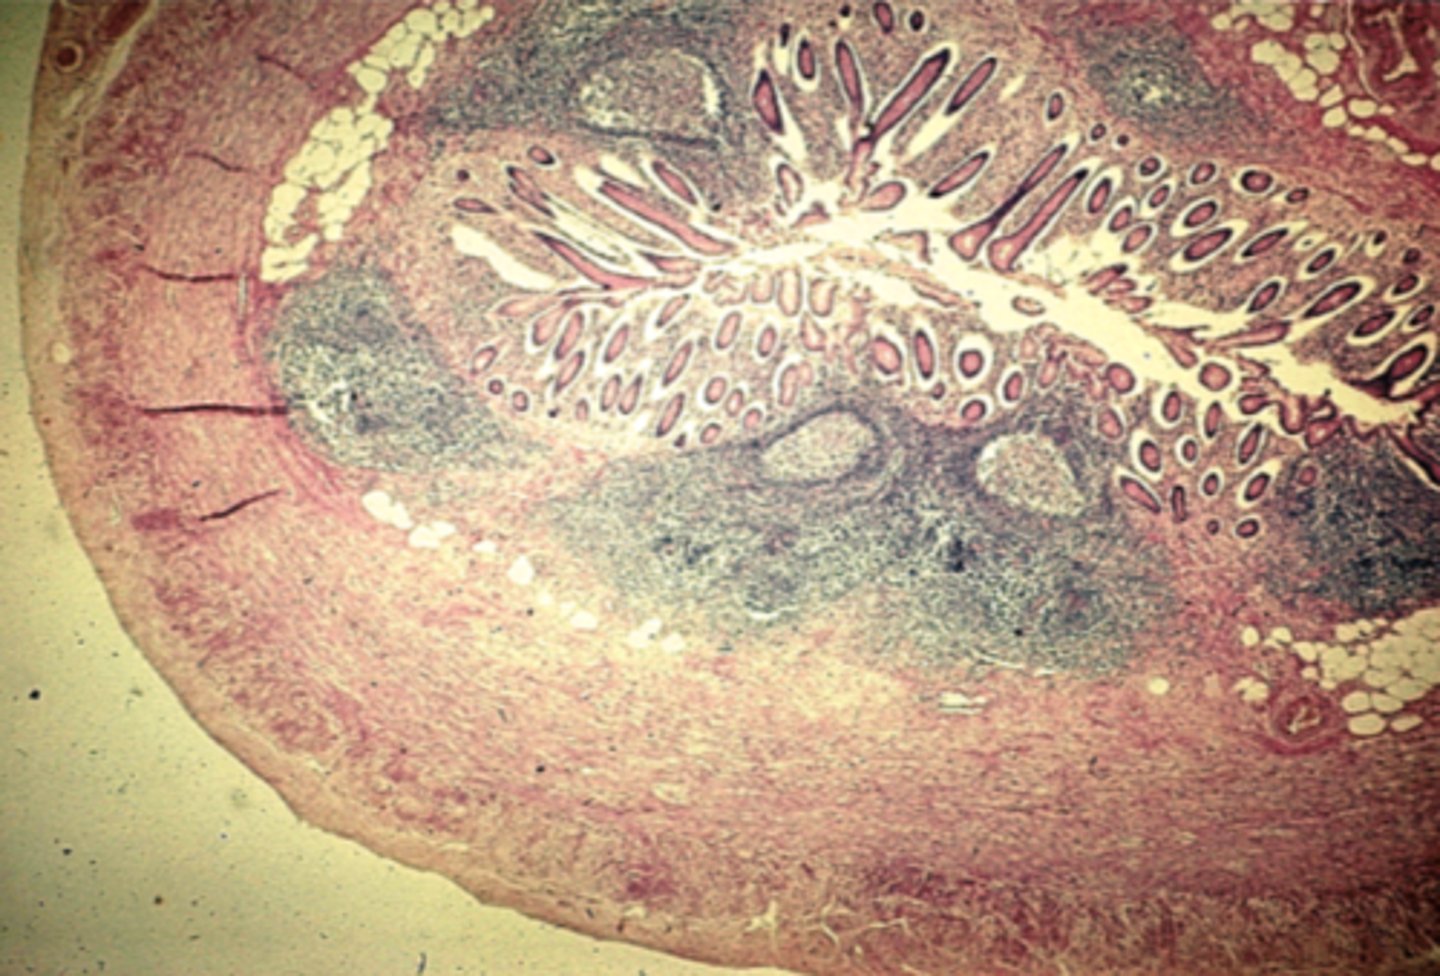

Appendix

What is this?

ileum

What is this?

ileum Peyer's patch

What is this?